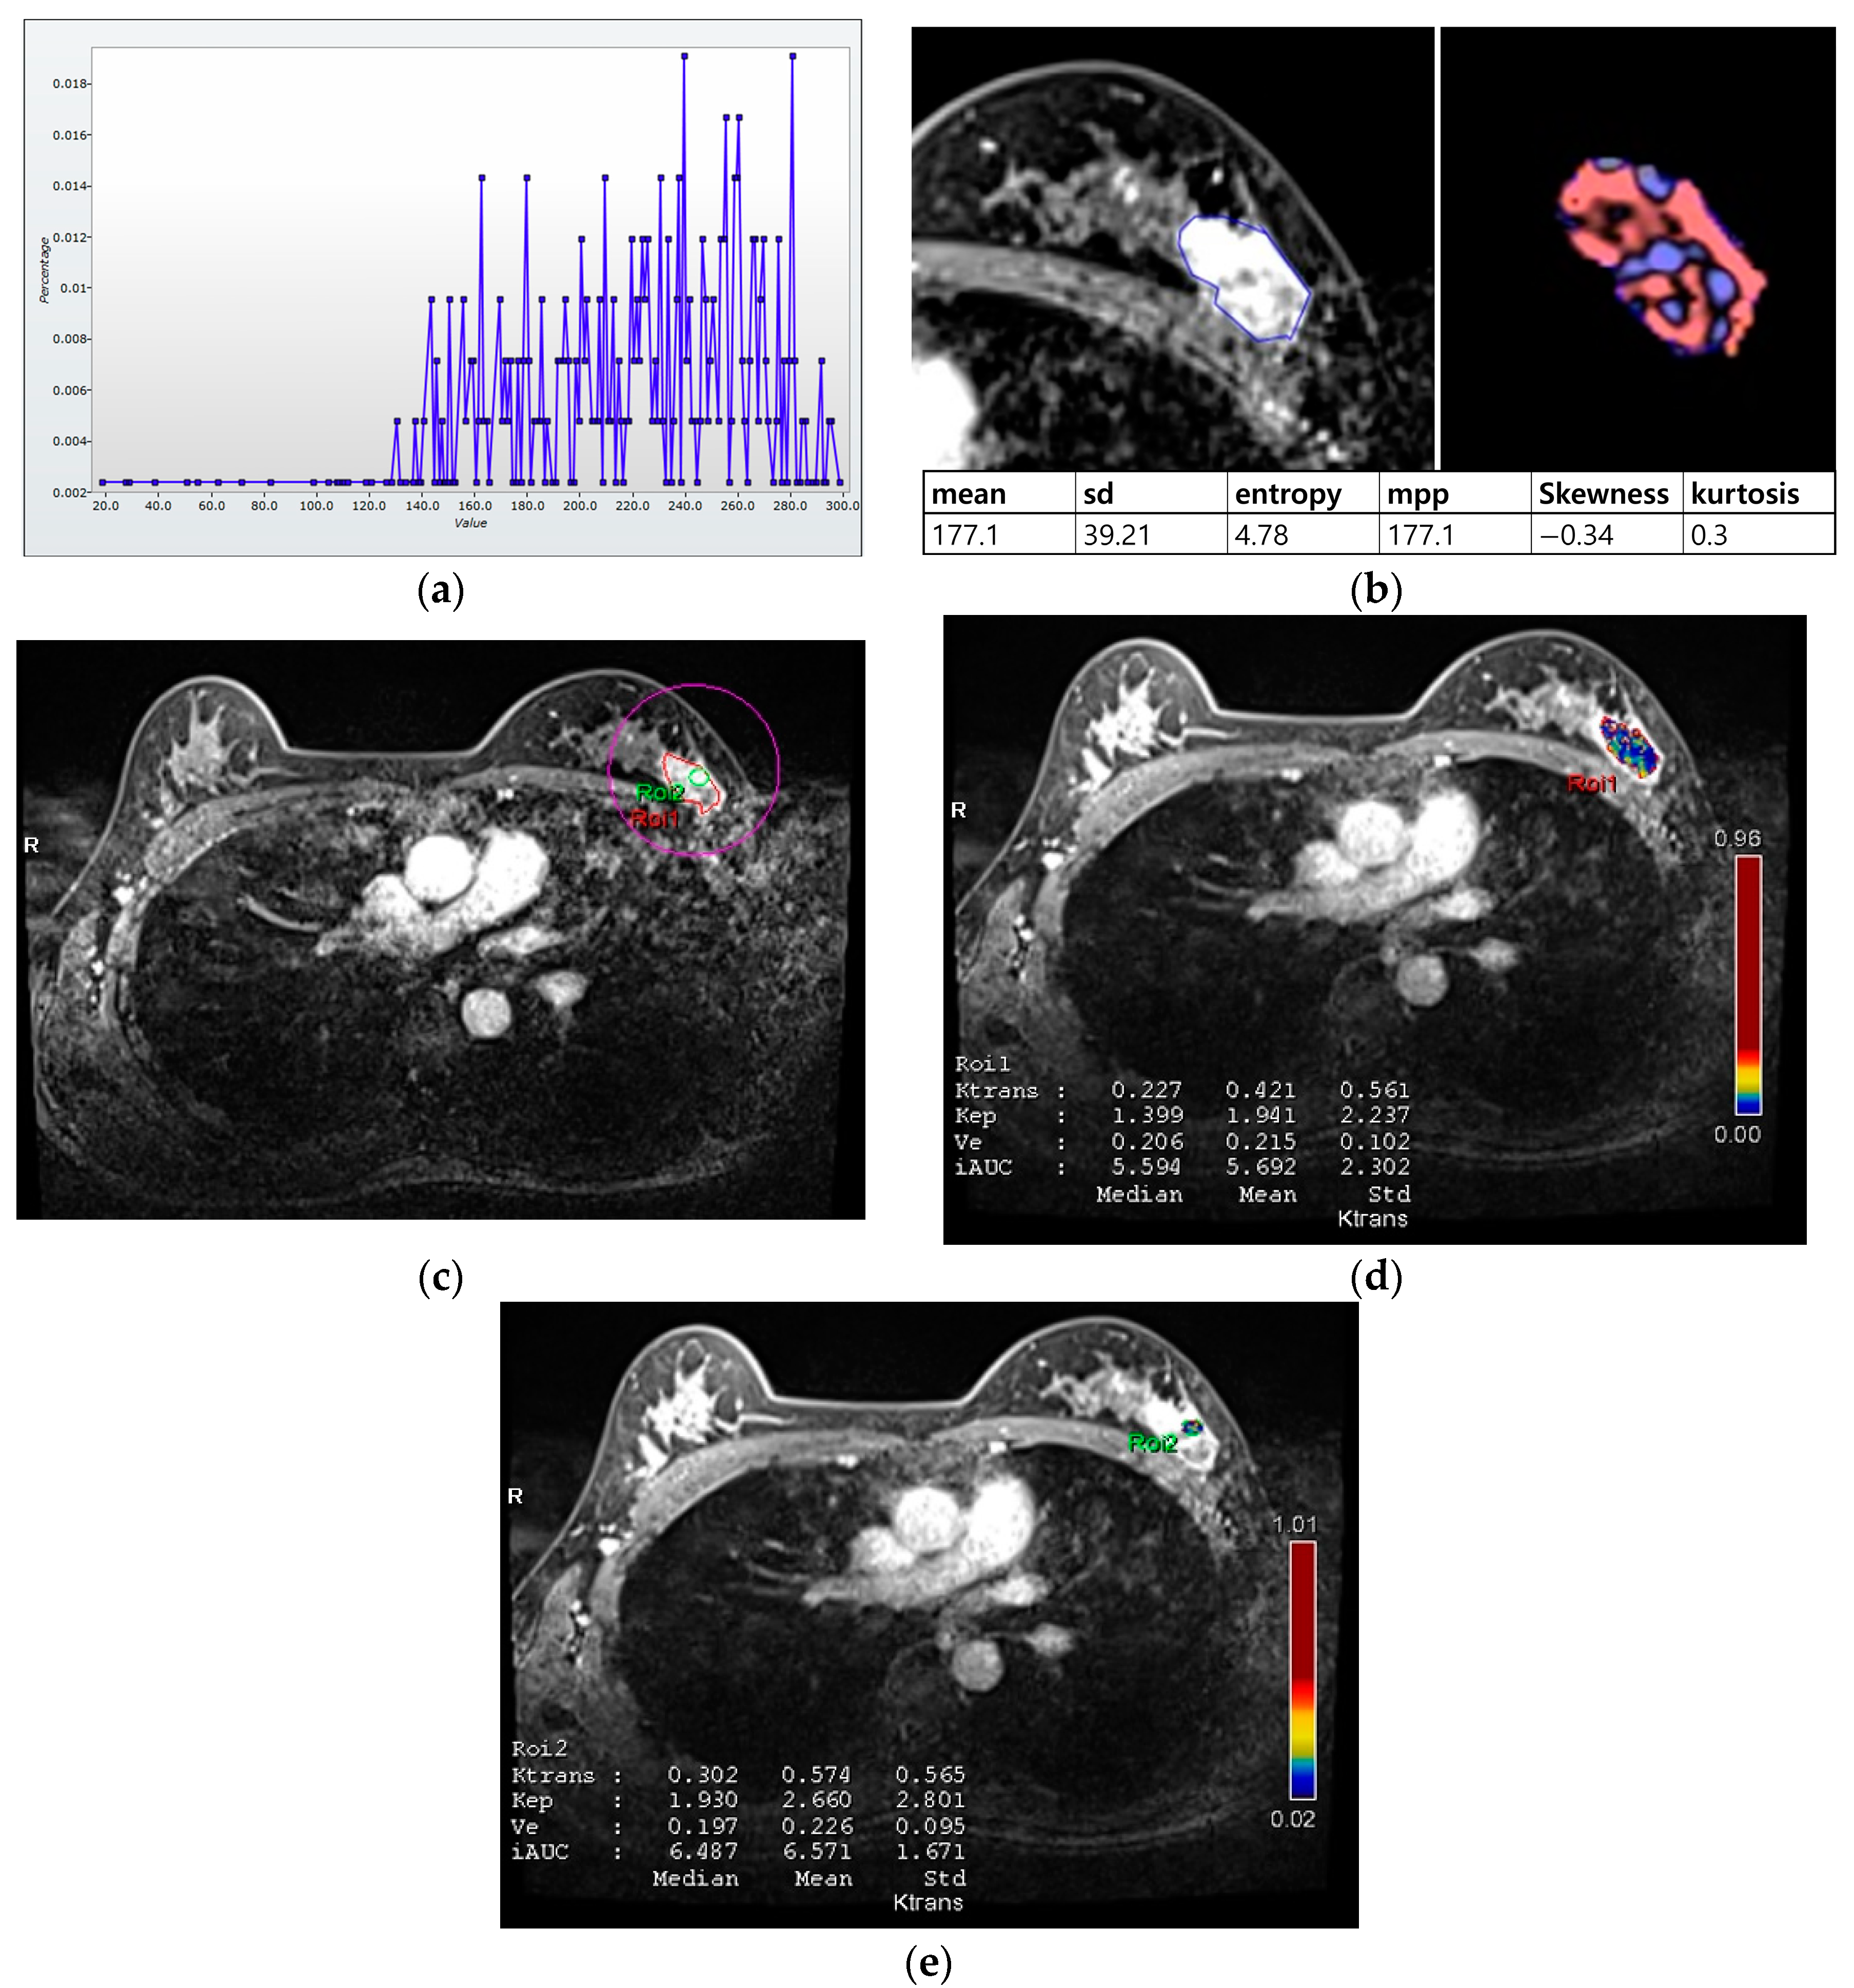

For histogram analysis, a region of interest (ROI) was drawn along the entire tumor enhancement on PostcontrastT1 in the largest cross-sectional area of the tumor, and this was then used for PrecontrastT1 and T2 lesions corresponding to those on PostcontrastT1. After tumor segmentation, six parameters were extracted from each ROI without filtering: (a) mean pixel intensity, (b) standard deviation (variation from the mean), (c) means of positive pixels (the average gray level intensity above zero threshold), (d) entropy (the randomness of gray-level distribution), (e) kurtosis (the peakedness of the distribution), and (f) skewness (asymmetry of the distribution) (Figure 2a,b).

Figure 2.

Histogram and perfusion analyses conducted on breast MRI in a 42-year-old woman with a 30 mm triple-negative invasive ductal carcinoma of the left breast (a,b). Histogram analysis on MRI: Axial contrast-enhanced T1-weighted MRI image shows an oval shaped, irregular marginated, and heterogeneous enhancing mass in the left breast. The region of interest (ROI) was drawn manually for the entire tumor, and a histogram was obtained (a). From the histogram, six statistically based metrics were extracted: mean, standard deviation (SD), mean of positive pixels (MPP), entropy, skewness, and kurtosis (b). (c–e) Perfusion analysis on MRI: Two ROIs (ROI1: entire tumor and ROI2: hot spot) were manually delineated (c), and eight perfusion parameters from each ROI were obtained: median and mean values of Ktrans, kep, Ve, and iAUC (d,e).

For perfusion analysis, measurements were made in two ROIs for the entire tumor and hot spot (high perfusion area within the tumor; Figure 2c–e). Perfusion parameters were calculated using voxel-wise T1 perfusion maps, gadolinium concentration–time, arterial course input function, and fitting with a pharmacokinetic model. Four perfusion parameters were extracted from two ROIs for each tumor: (a) Ktrans (the constant representing the transfer of contrast medium from blood plasma to the extracellular extravascular space per minute), (b) kep (the rate constant representing transfer of contrast medium from the extracellular extravascular space into blood plasma per minute), (c) Ve (the extracellular extravascular space per unit volume of tissue), and (d) iAUC (the initial area under the contrast concentration–time) [,,]. The hot spot was selected as the high perfusion area on the Ktrans-based perfusion map. The median and mean values of each parameter were automatically calculated from the two ROIs.